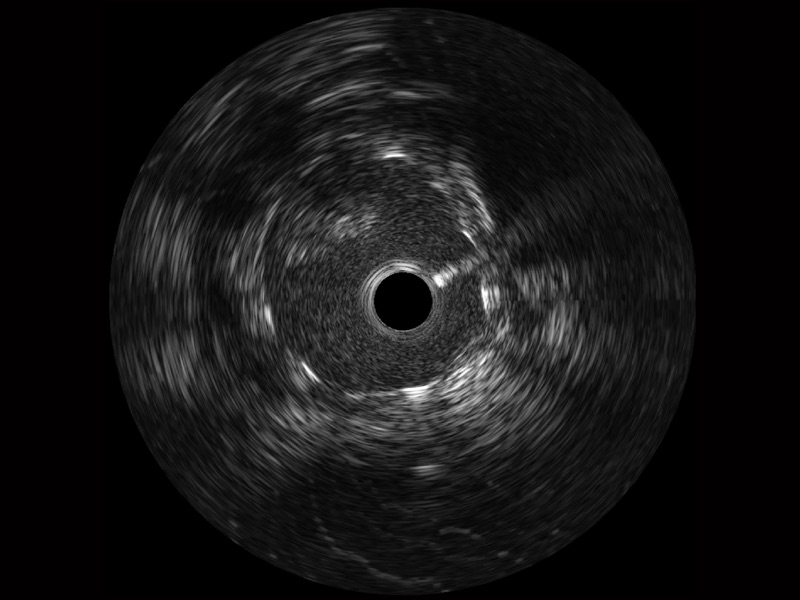

DB中国旗舰官方网站宽频IVUS图像

对比传统IVUS导管成像,DB中国旗舰官方网站宽频IVUS图像的近场支架梁显影更细腻,远场中膜外血管仍清晰可辨,兼顾远中近,兼顾分辨力与穿透深度